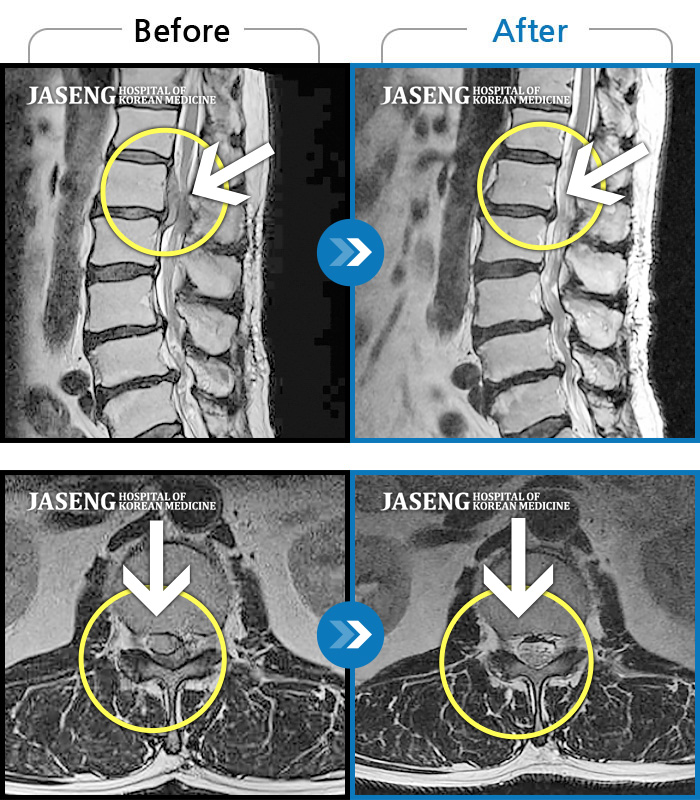

허리디스크

수원 · 김태성 원장

허리 통증과 우측 고관절~하지방사통이 심하여 활동하기 힘든 상태

촬영시기

2021.03.04 ~ 2021.10.06

2022.03.25